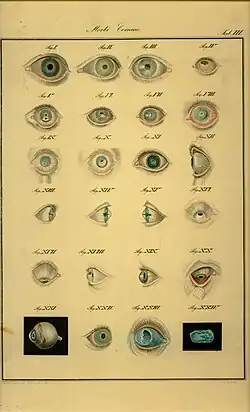

Аммон издавал два журнала: «Zeitschrift für Ophtalmologie» (5 т., Дрезден и Гейдельберг, 1830—36) и «Monatsschrift für Medizin, Augenheilkunde und Chirurgie» (3 том, Лейпциг, 1838—40). Помимо статей размещённых в этих журналах, Аммон опубликовал некоторые труды отдельными изданиями. Написанный им атлас глазных болезней одно время был наиболее подробным иллюстрированным пособием по офтальмоскопии.

- «Klinische Darstellungen der Krankheiten und Bildungsfehler des menschlichen Auges» (4 т., Берлин, 1838—1847);